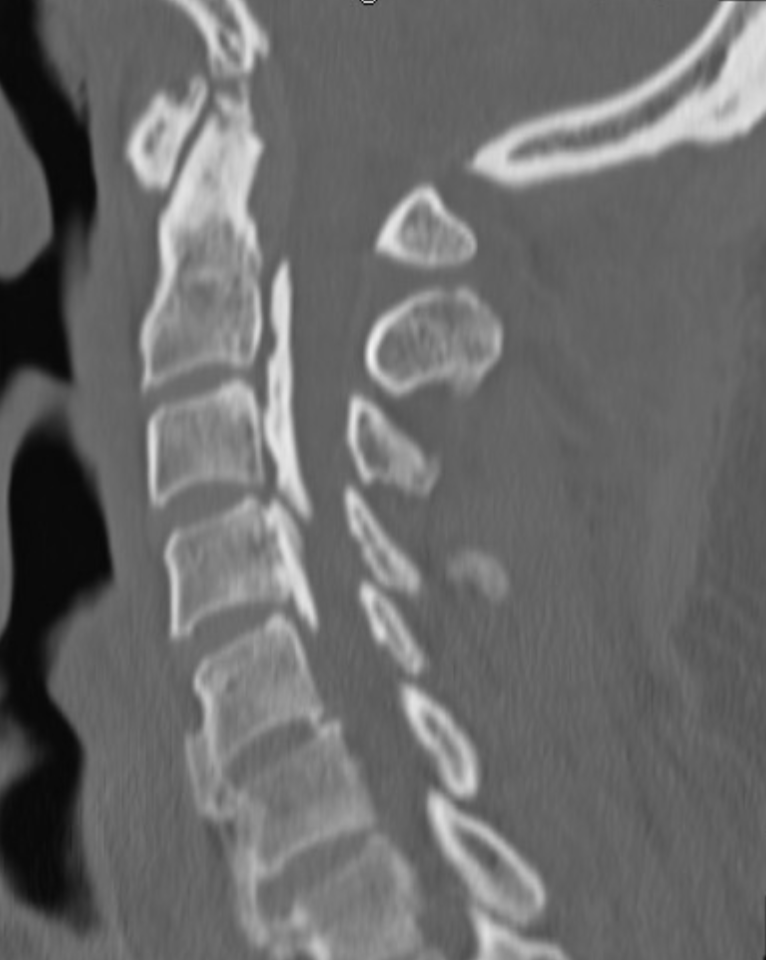

- CT scan: Helpful in assessing bony compression and OPLL